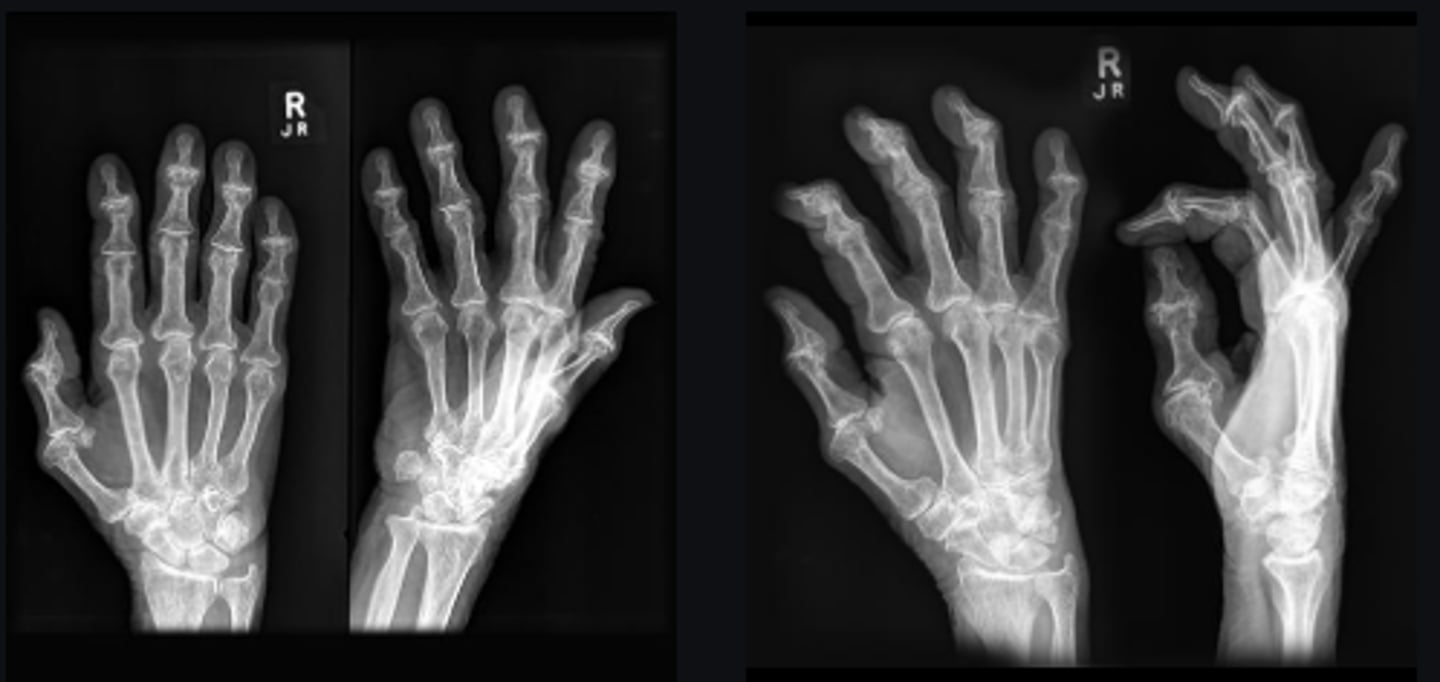

DIPs

Joint

Yes

Joint space narrowed?

Non-uniform

Uniform/non-uniform joint narrowing

No

Periarticular erosions

Osteophytes

A little bit

Subchondral cysts

Subchondral sclerosis

Periarticular osteopenia

Not a lot

Soft tissue swelling

Intra-articular calcification

Joint ankylosis

Extra-articular calcification/osseous bodies

Subluxation

Dislocation/diastasis

Degenerative

Category of disease

Osteoarthrosis

Diagnosis?

Heberden's nodes

Clinically, what may be noted by inspecting the involved joints?